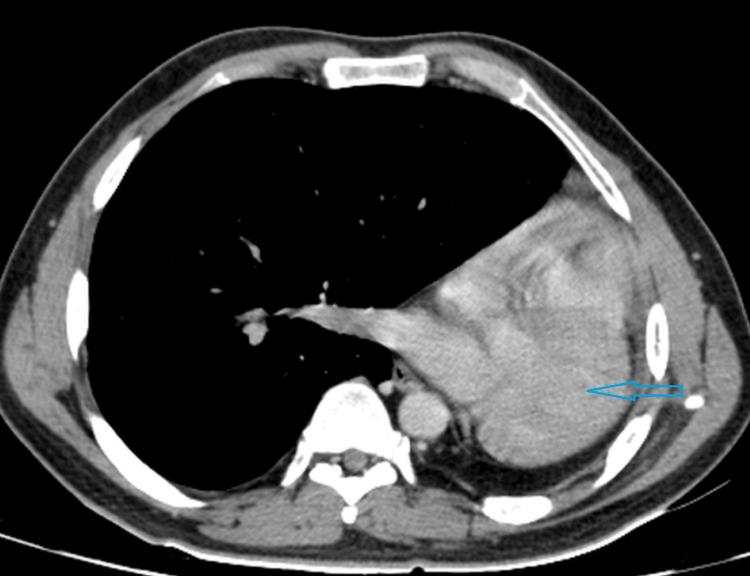

Pulmonary agenesis is a rare congenital condition where there is no development of pulmonary tissue beyond the carina. One or both lungs may be involved, but bilateral involvement is not compatible with extra-uterine existence. If one lung is involved, it is most commonly the left side. However, right lung involvement is more frequently associated with other inborn anomalies and severity in presentation. Here, we report a 19-year-old male patient having complete agenesis of the left lung, presenting with recurrent episodes of nonspecific cough, without fever and dyspnea on exertion. His vitals were stable on examination, and all routine laboratory blood tests were normal. Chest auscultation revealed the absence of breath sounds in most of the left hemithorax. Chest wall movement was less compared to the right side. A chest radiograph was advised, which showed opacity in the left hemithorax, suspicious of a collapsed lung with mediastinal shift. To determine the nature of the opacity, a computed tomography (CT) scan of the chest was conducted, revealing complete agenesis of the left lung, along with ipsilateral shift of the heart and compensatory hyperinflation of the right lung. Unilateral lung agenesis may remain asymptomatic until adulthood. Radiological investigations like chest radiograph may be useful in the diagnosis, but a CT scan of the chest can confirm the diagnosis with status of the pulmonary vasculature and bronchial tree.

肺不发育是一种罕见的先天性疾病,在隆突以下没有肺组织发育。一侧或双侧肺可能受累,但双侧受累与宫外生存不相符。如果一侧肺受累,最常见的是左侧。然而,右侧肺受累更常与其他先天性异常及临床表现的严重程度相关。在此,我们报告一名19岁男性患者,其左肺完全不发育,表现为反复出现的非特异性咳嗽,无发热及劳力性呼吸困难。检查时生命体征稳定,所有常规实验室血液检查均正常。胸部听诊发现左半侧胸廓大部分区域呼吸音消失。与右侧相比,胸壁活动较少。建议进行胸部X线检查,结果显示左半侧胸廓不透光,怀疑肺萎陷伴纵隔移位。为确定不透光区的性质,进行了胸部计算机断层扫描(CT),结果显示左肺完全不发育,同时心脏向同侧移位,右肺代偿性过度充气。单侧肺不发育在成年前可能一直无症状。胸部X线等影像学检查对诊断可能有用,但胸部CT扫描可通过肺血管系统和支气管树的情况确诊。